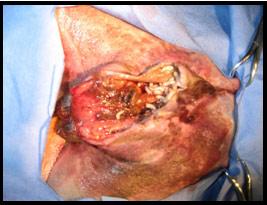

Le traitement consiste à corriger le problème primaire ( plaie, infection, malpropreté). Les plaies sont rasées et nettoyées. Les larves doivent être retirées. Si l’état de l’animal le permet, un débridement ( nettoyage) de la plaie sous anesthésie est la méthode la plus efficace pour éliminer les larves. Certains medicaments peuvent être donnés pour tuer les larves, conbattre l’infection bactérienne et pour diminuer la douleur et l’inflammation.